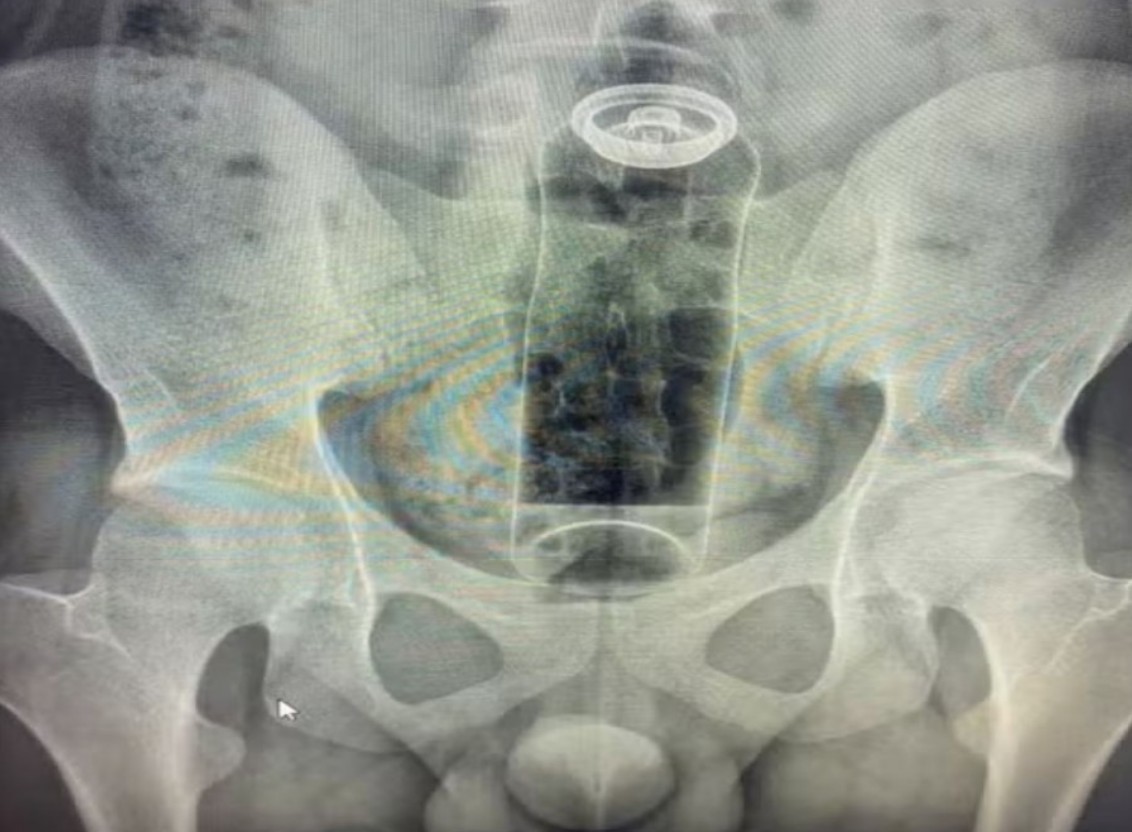

Fibrose Pulmonar Idiopática

Uma das doenças raras com maior incidência entre os brasileiros, é uma doença crônica não infecciosa, sua causa ainda é desconhecida. Atinge entre 10 e 20 pessoas a cada 100 mil. a progressão da doença se dá de forma lenta e gradual, em alguns casos há uma progressão mais acelerada, dentro de poucos meses. A Fibrose Pulmonar Idiopática é fatal, tendo o paciente entre 2 e 4 anos de vida após o diagnóstico que é feito através de avaliação da função pulmonar ou de biópsia pulmonar, onde um pequeno fragmento do pulmão é retirado cirurgicamente. O perfil médio de pacientes afetados estão na casa dos 60 anos, maiora do sexo masculino, fumantes ou ex-fumantes.

A síndrome é causada por um erro metabólico, devido a ausência de uma enzima responsável pelo metabolismo de mucopolissacarídeos específicos, resultando num acúmulo dessas substâncias no organismo dos pacientes. A doença afeta principalmente pacientes do sexo masculino. Segundo o site huntersyndrome.info, os principais sintomas da síndrome são desproporção de traços faciais, infecções respiratórias e coriza crônica (secreção nasal constante). Os sintomas aparecem entre 2 e 4 anos de idade, e o diagnóstico precoce é de fundamental importância. Nos Estados Unidos, cerca de 500 pessoas sofrem com a síndrome e aproximadamente 2 mil no mundo todo.